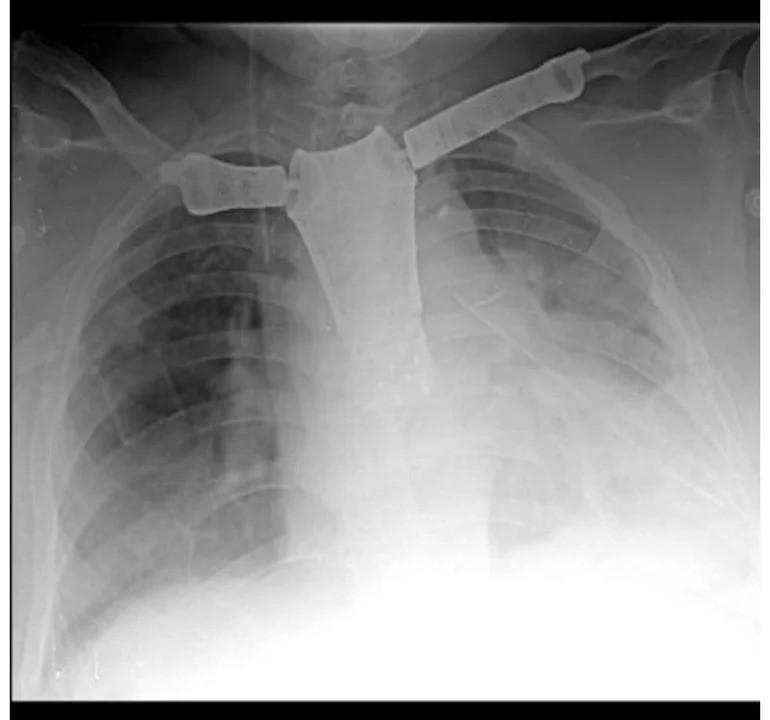

La paciente, una mujer de 61 años procedente de Miramar, fue sometida a esta operación innovadora después de ser diagnosticada con un tumor maligno en la pared torácica que comprometía el esternón, ambas clavículas y la primera costilla izquierda.

El procedimiento implicó la extirpación del tumor y la reconstrucción de las áreas afectadas, incluida la sustitución del esternón, las clavículas y las articulaciones con prótesis de titanio fabricadas mediante impresión 3D. Este enfoque quirúrgico único permitió preservar la movilidad articular de las clavículas, lo que promete una mejor calidad de vida para la paciente en su recuperación.

La empresa RAOMED desarrolló la prótesis personalizada en impresión 3D, que fue fundamental para el éxito de la intervención. Durante las 7.5 horas de cirugía, se llevó a cabo la resección del tumor con márgenes oncológicos adecuados, seguida de la colocación de la prótesis y la cobertura con colgajos musculares.